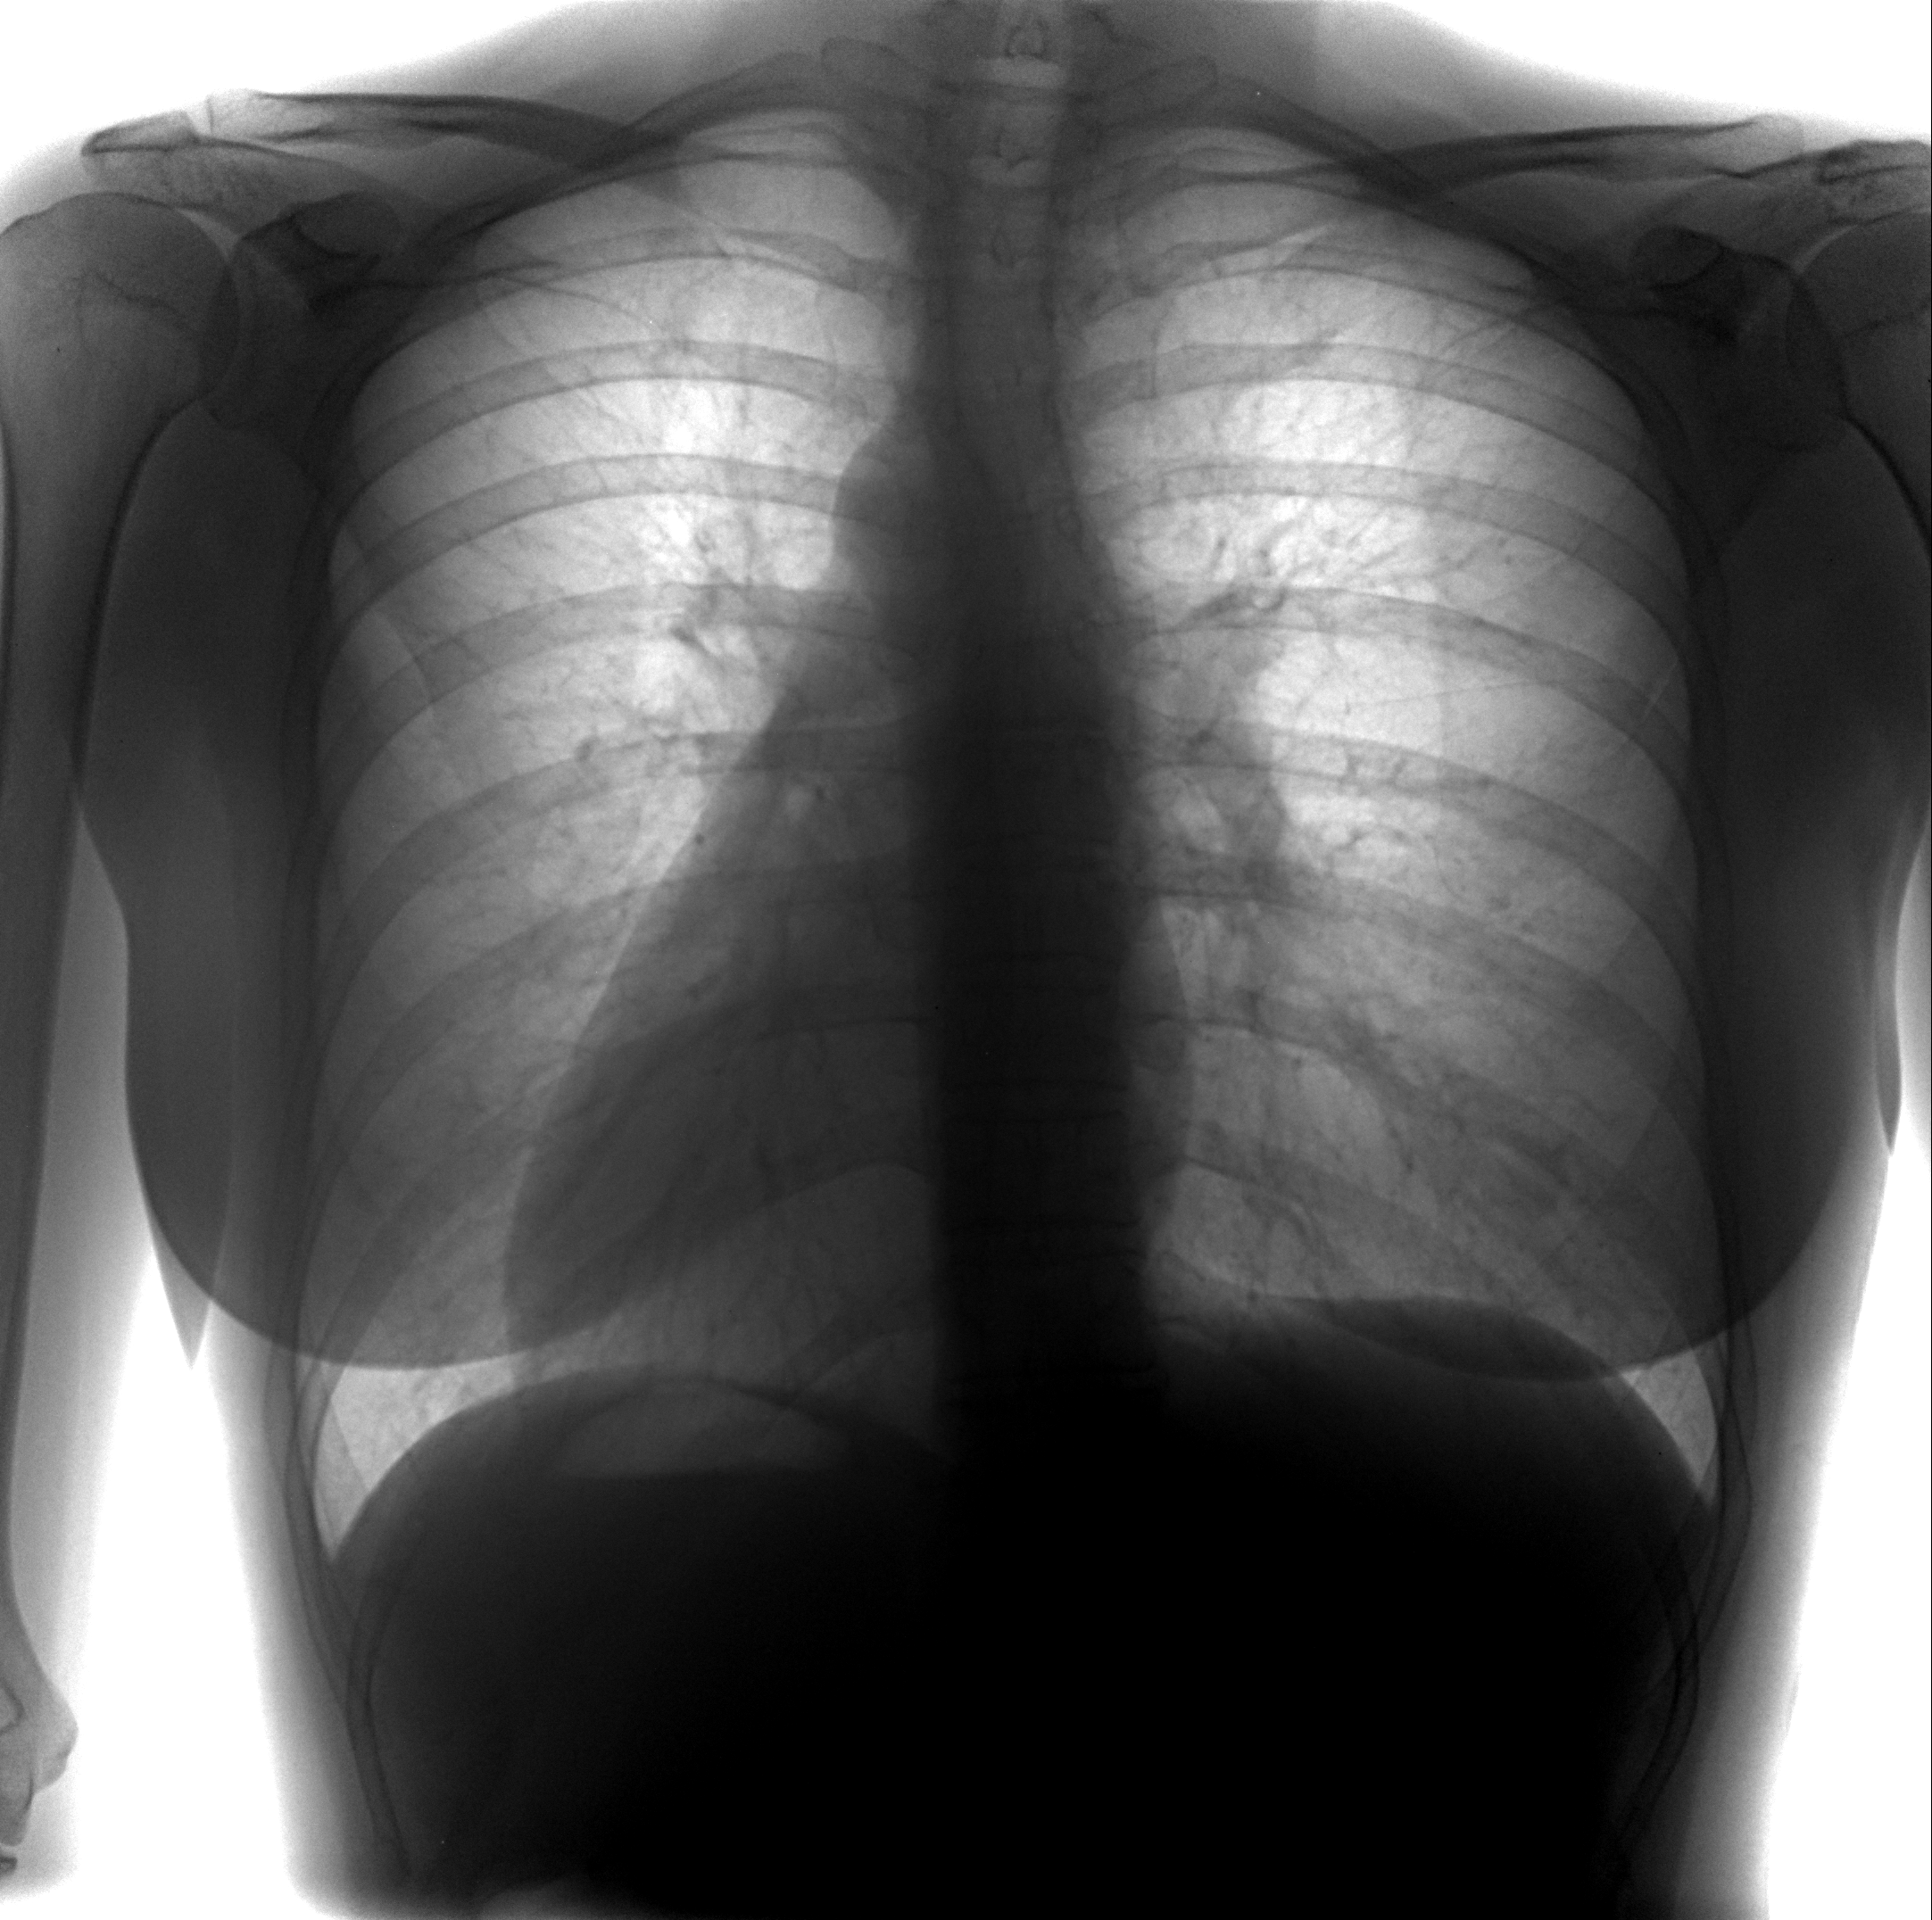

Нормальная рентгенограмма легких: что нужно знать

Раздел: Мудрость в объективе